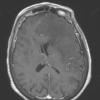

NEOPLASMS (GLIAL)

Astrocytoma, IDH-mutant, WHO Grade 2 (9)